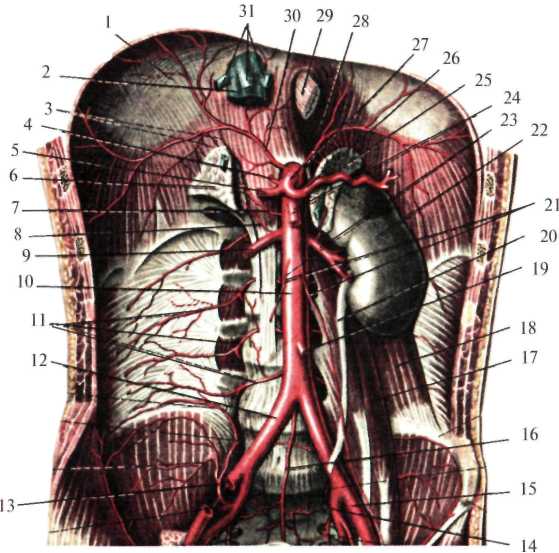

Брюшная аорта (aorta abdominalis) на уровне XII грудного позвонка, пройдя через аортальное отверстие диафрагмы (hiatus aorticus diaphragmatis), вступает в забрюшинное пространство, располагаясь несколько левее от средней линии, и на уровне IV поясничного позвонка делится на правую и левую общие подвздошные артерии (рис.2.8). Кпереди от аорты лежит поджелудочная железа, восходящая часть 12-перстной кишки и корень брыжейки тонкой кишки, справа – нижняя полая вена, слева – поясничная часть левого симпатического ствола.

От брюшного отдела аорты отходят парные и непарные ветви. Последние берут начало от передней поверхности аорты. К ним относятся: чревный ствол (truncus coeliacus), отходящий от аорты на уровне XII грудного позвонка, верхняя брыжеечная артерия (a. mesenterica superior) – I поясничного позвонка, нижняя брыжеечная артерия (a. mesenterica inferior) – III-IV поясничных позвонков, а также может быть средняя крестцовая артерия (a.sacralis mediana).

Парные ветви отходят от боковых стенок аорты: нижние диафрагмальные артерии (aa. phrenicae inferiores), средние надпочечниковые артерии (aa. suprarenales mediae), почечные артерии (aa. renales), яичковая или яичниковая артерии (a. testiculariss, s. ovarica), 4-е пары поясничных артерий (aa. lumbales).

Рис. 2.8. Ветви брюшной аорты (по Синельникову, с изменениями).

1 – diaphragma; 2 – v. cava inferior; 3 – aa. suprarenales superiores; 4 – a. gastrica sinistra; 5 – a. hepatica communis; 6 – gl. suprarenalis dextra; 7 – a. suprarenalis media; 8 – a. suprarenalis inferior; 9 – a. renalis dextra; 10 – aorta abdominalis; 11 – aa. lumbales; 12 – a. iliaca communis dextra; 13 – a. iliolumbalis; 14 – a. iliaca interna sinistra; 15 – a. iliaca externa sinistra; 16 – a. sacralis mediana; 17 – m. psoas major; 18 – m. quadratus lumborum; 19 – a. mesenterica inferior; 20 – ureter; 21 – aa. testiculares dextra et sinistra; 22 – ren;

23 – a. renalis sinistra; 24 – a. mesenterica superior; 25 – gl. suprarenalis sinistra; 26 – a. splenica; 27 – truncus coeliacus; 28 – a. phrenica inferior sinistra; 29 – oesophagus; 30 – a. phrenica inferior dextra; 31 – vv. hepaticae